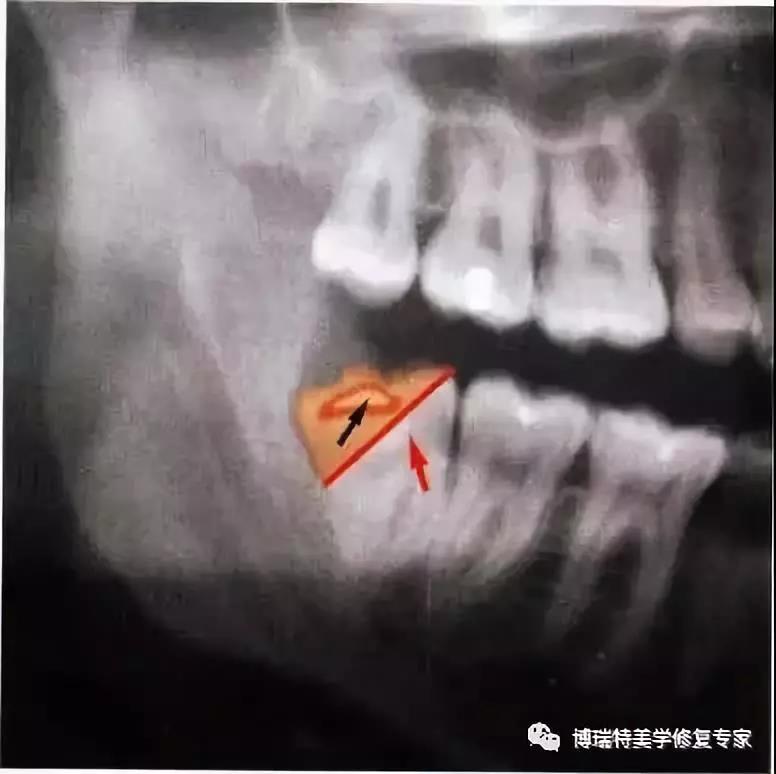

1、下颌第三磨牙阻生。代表牙槽窝深度的红线表明从牙槽嵴顶到釉牙骨质界间在近中颊角方向上的距离。考虑到患者的年龄,阻生牙牙槽窝的近中骨壁较容易以第二磨牙牙根旁的硬骨板为基础分化再生。因此,该患者第二磨牙牙槽骨修复重建的预后较好。

2、阻生牙(牙合)面上覆盖的软组织较完整,牙槽窝与口腔不相通。切口起点应位于颞肌嵴黏膜,前庭沟的舌侧,朝向距离第二磨牙远中面15 mm外缘处向前切开。

3、翻开黏骨膜瓣显露牙槽嵴。图中已将黏骨膜瓣翻开,在舌侧开窗去骨显露阻生牙的远中颊尖,再通过装在机头上的外科圆钻去除覆盖于(牙合)面的骨质。

4、将牙冠颊侧大部分显露至釉牙骨质界时方能较全面地认识该阻生牙在牙槽窝内的位置。根尖片只能显示该阻生牙在(牙合)面的投影而不能显示其颊舌向倾斜的情况。在低位舌侧近中阻生时,阻生牙同时与邻牙牙根的远中壁和舌侧骨板相接触,故舌侧骨板必然较为薄弱甚至被穿透。(出现骨开窗)

5、由于根分叉较小且较低,第二磨牙牙冠的位置阻碍了车针的正确安放,并且有破坏舌侧骨板的危险。在这种情况下,临床医师从近中颊角开始切割近中部分牙体,这种方法不存在任何风险而且只需要短短的几秒钟。

6、阻生牙仍被远中牙槽嵴所阻挡,故去除远中部分牙冠,使牙顺利向远中颊向脱位。